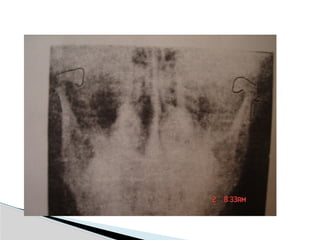

Conventional Radiology

At least 2 views at right angle to each other.

Mandibular series: PA, Lateral oblique or

panoramic, & Towne’s view (projects condyle

below mastoid process).

Conventional Radiology At least2 views at right angle to each other. Mandibular series: PA, Lateral oblique or panoramic, & Towne’s view (projects condyle below mastoid process). CT Significant displacement or dislocation, mechanical obstruction, mult trauma pt, & intracapsular fracture. MRI St injuries: effusion, visualization of disc. Imaging